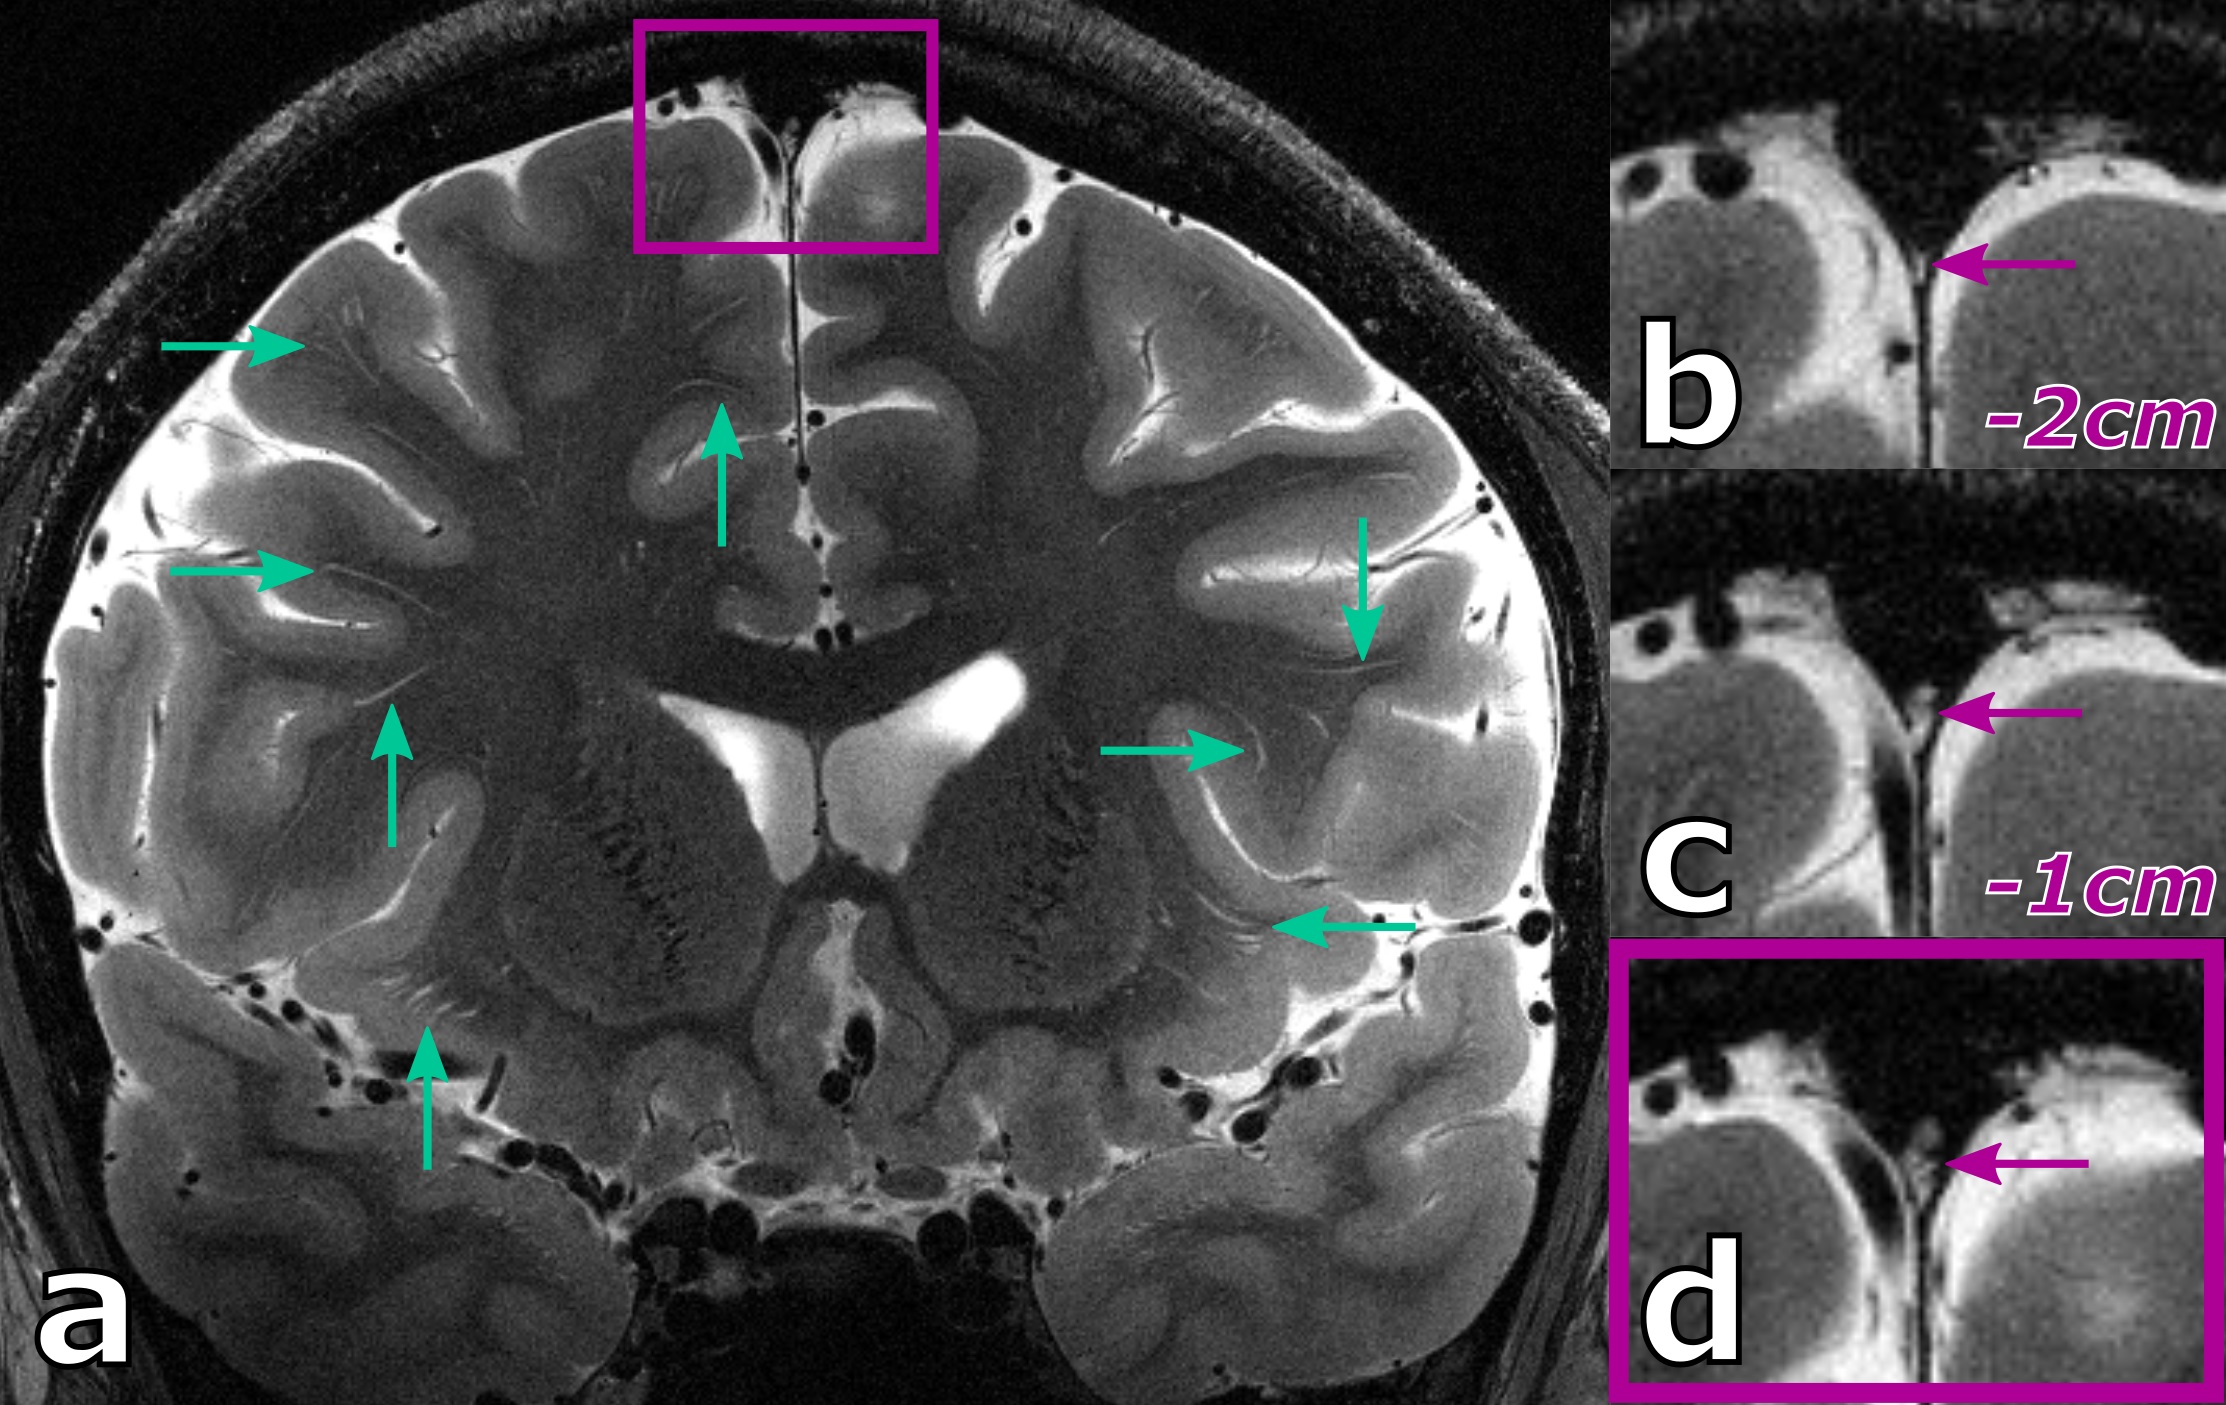

Figure 1: Ultra high resolution, coronal slices of a healthy 27 years old male showing perivascular spaces (green arrows) as well as the parasagittal dura (magenta box) with the zoomed in version shown in (d). Additionally, slices positioned 1 and 2 cm further posterior show how the hyperintense structure (magenta arrow) is propagating into the sinus